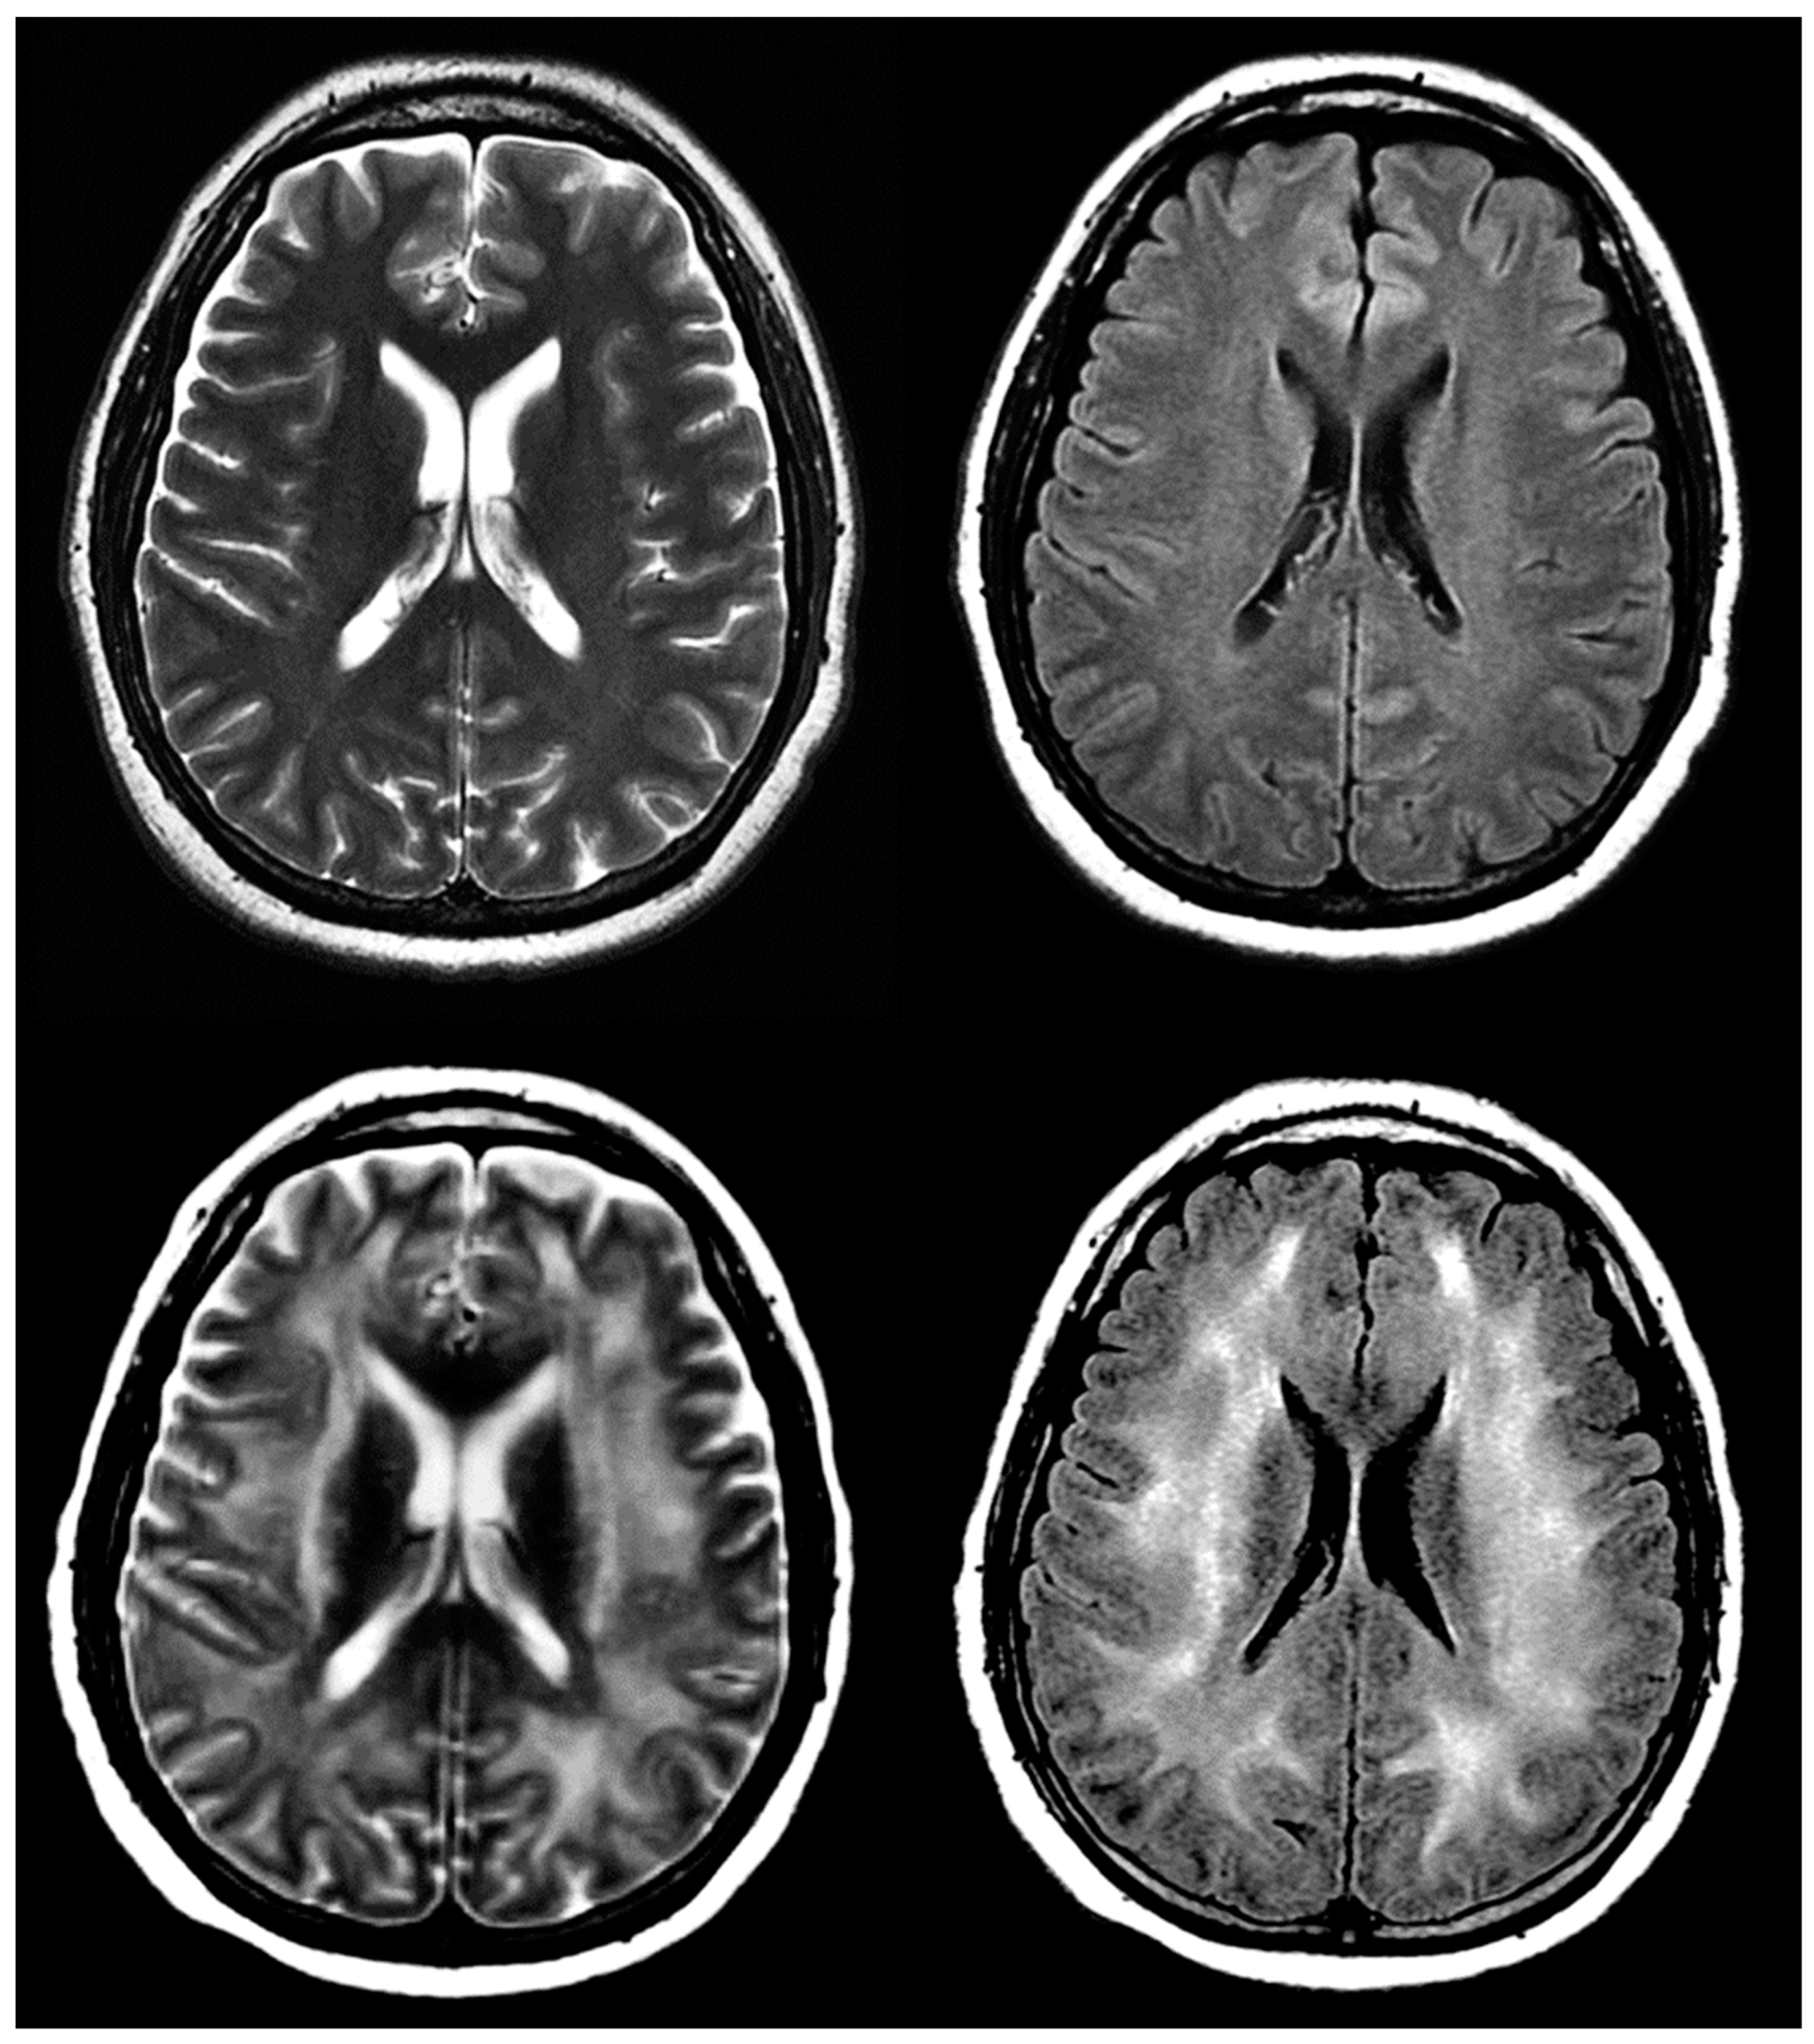

ICANS is the second most common CAR T-cell IRAE after CRS. Onset is most often four days after infusion, and includes a variety of neural symptoms, some severe: encephalopathy, headache, tremor, and aphasia. The onset of symptoms often overlaps with CRS [70]. MRI is the imaging modality of choice for evaluating ICANS due to its superior resolution to CT. Long-term follow-up is recommended to assess for potential cerebral damage [73] (Figure 7).

Figure 7.

A 43-year-old woman with acute myeloid leukemia and history of confusion and disorientation 7 days post-treatment with CAR T-cells. Select images from axial T2 and FLAIR sequences pre- (above) and post- (below) CAR T-cell therapy demonstrating diffuse hyperintense signal abnormality in subcortical and supratentorial white matter, suspected for ICANS.